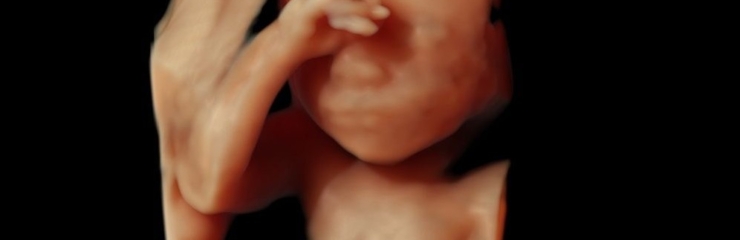

Шейные позвонки хорошо видны. На 23-й неделе плод весит примерно 550 граммов. С 23-й недели на 4D-ультразвуковом исследовании уже можно хорошо рассмотреть черты лица плода.

- По желанию — 4D-ультразвуковое исследование (24–32 недели)

Вес плода составляет примерно 1 килограмм, длина — около 35 сантиметров. Это лучшее время для наблюдения лица плода с помощью 4D-ультразвукового исследования.

Это время, когда стоит постепенно начинать думать о родах и обсудить, кого женщина хотела бы видеть в качестве сопровождающего на родах. В этот период можно вместе сходить на 4D-ультразвуковое исследование, которое даёт информацию о здоровье и развитии ребёнка, а также позволяет будущим родителям наблюдать за своим малышом в реальном времени, вызывая радость и положительные эмоции.